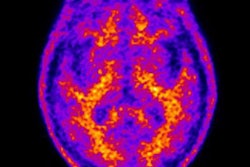

Previous studies have shown that PET scans of the brain can identify the accumulation of beta-amyloid plaque and tau tangles that are associated with the onset of cognitive impairment, dementia, and Alzheimer's disease.

PET shows the average florbetapir uptake per mouse group at 8 and 13 months of age. A significant interaction of genotype treatment was observed in the cortex (p = 0.0248), hippocampus (p = 0.0071), and thalamus (p = 0.0084), indicating reduced florbetapir uptake in BACE1-inhibited mice. WT = wild type (controls); TG = transgenic (genetically modified). Image courtesy of the Molecular Imaging Center Antwerp and JNM.All three tracers detected pathological differences between the genetically modified mice and the controls; however, only florbetapir illustrated the effects of inhibitor treatment by identifying reduced beta-amyloid pathology in the genetically modified mice, as confirmed by the microscopic studies.